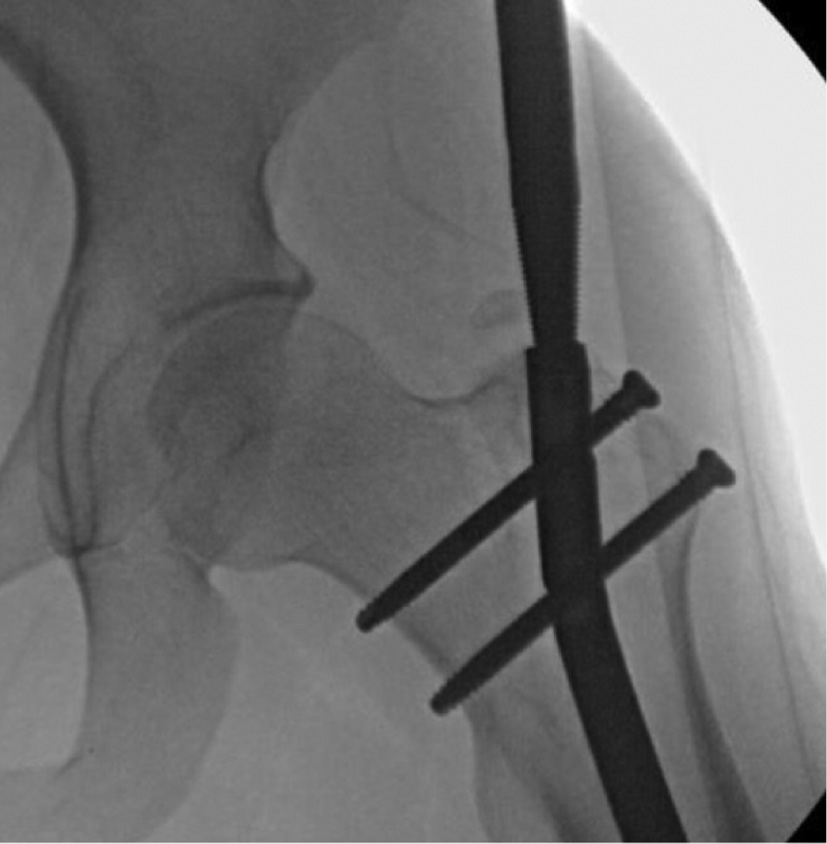

4. Once one of the distal screws/pegs is removed, the nail insertion incision is re-opened and a 3.2 mm K-wire is placed through the patella tendon (Figure 23). It is important that the guidewire is aligned perfectly to the center of the nail under fluoroscopy in both the coronal and sagittal planes (Figure 24). The K-wire can be tapped in using a mallet (Figure 25). It is helpful to have the fluoroscope in the AP plane aligned orthogonal to the limb (Figure 26).

5. An incision along the K-wire through the patella tendon is performed (Figure 27). The 12 mm cannulated cone is inserted over the K-wire through the patella tendon to the femoral notch (Figures 28 and 29). The hitting device for cone insertion (Figure 30) is used to place the cone’s thick part close to the bone (Figure 31). The 13/12 medium size tube is inserted over the cone through the joint and fixed in place by using a 12 mm hitting device (Figure 32). Tap the hitting device until it sits tight in the bone, but make sure it is not contacting the cable (Figure 33). The hitting device and cone are now removed, leaving the K-wire in place (Figure 34). The tube remains inserted in the bone to ensure clear passage and prevent any debris from passing into the knee joint during nail removal. The 12 mm straight motorized nail reamer is used to open a canal to the nail (Figure 35). The reamer is run until it just begins to contact the cable (Figure 36). The reamer and K-wire are now removed leaving the tube in place.

Figure 23. Once one of the distal screws/pegs is removed, the nail insertion incision is re-opened and a 3.2 mm K-wire is placed through the patella tendon.

jposna20220031_fig23.jpg

Figure 24. It is important that the guidewire is aligned perfectly to the center of the nail under fluoroscopy in both the coronal and sagittal planes.

jposna20220031_fig24.jpg

Figure 25. Tap the K-wire into the distal end of the nail with a mallet.

jposna20220031_fig25.jpg

Figure 26. It is helpful to have the fluoroscope oriented perpendicular to the plane of the distal femur.

jposna20220031_fig26.jpg